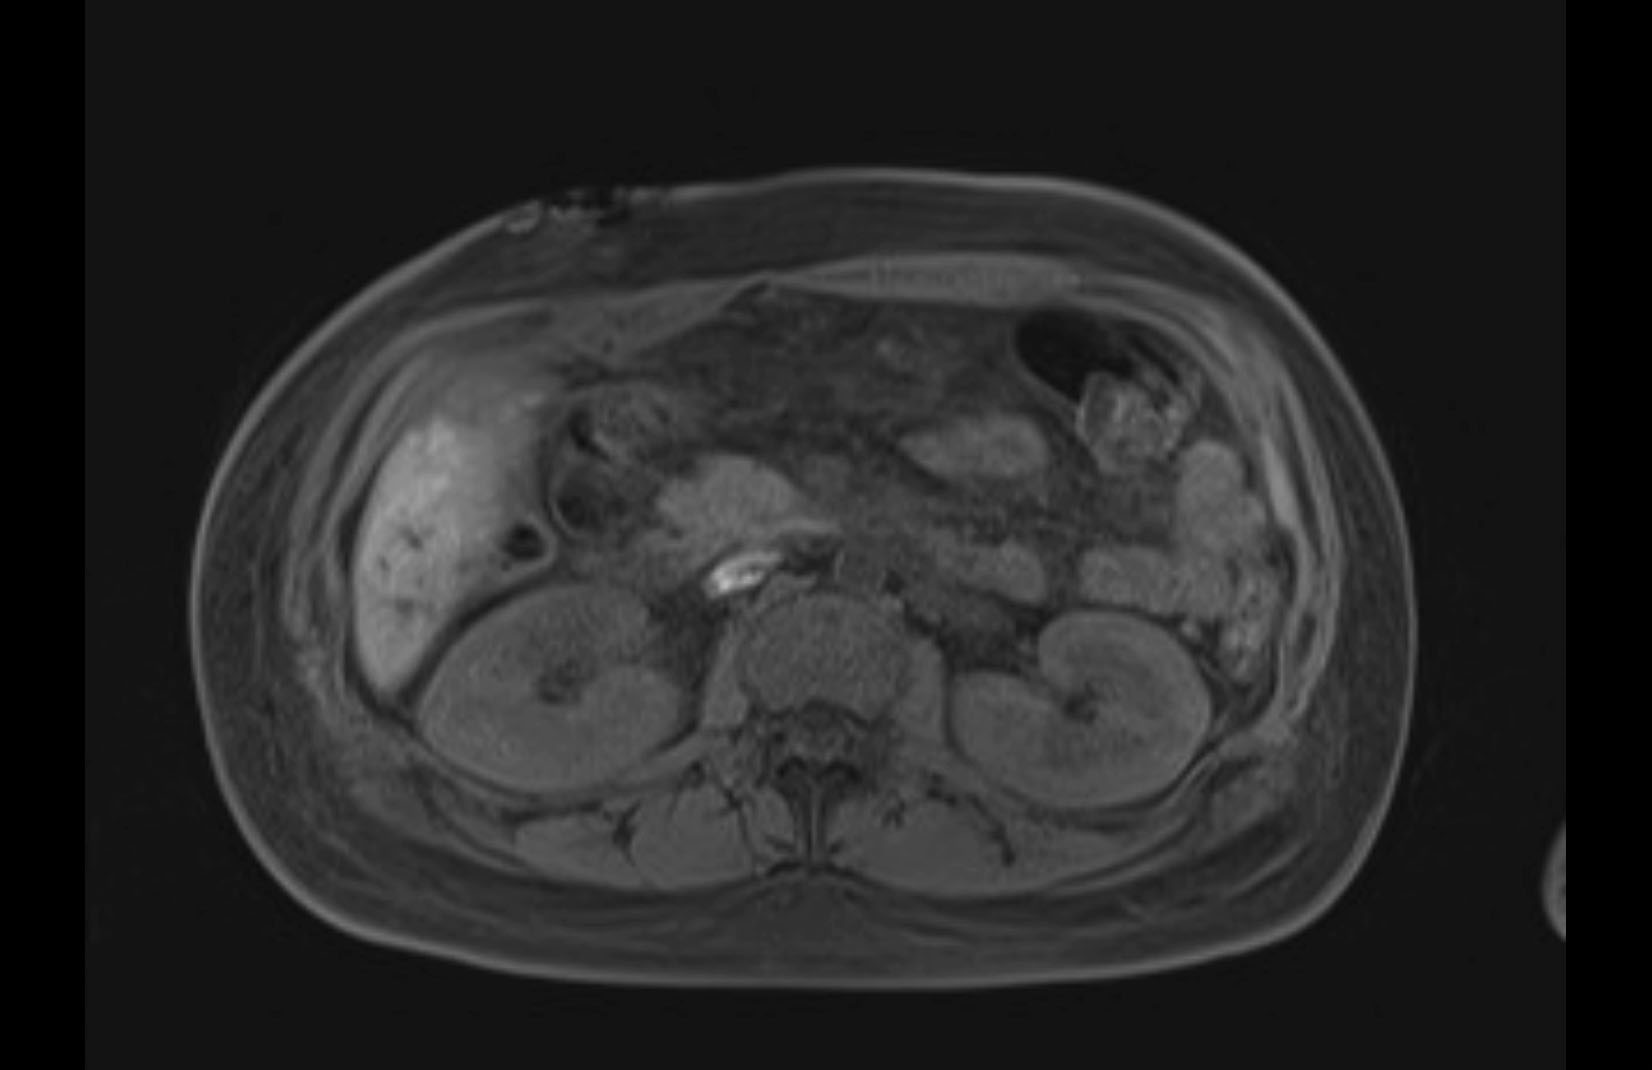

Imaging Analysis

Look through the patient's CT scan to identify any areas of concern for the necessary procedure.

MRI T1

Based on initial findings, which issue(s) would you be most concerned about?